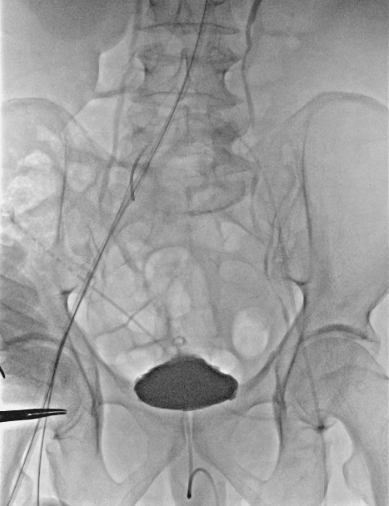

手术过程

1、穿刺患者左侧颈动脉与右股动脉,并在左颈动脉置入7F的穿刺鞘后,导入软导丝,自上而下地探索真腔,在穿出右股动脉后,从左股动脉导入9F长鞘至降主动脉,先后在长鞘内交换导丝为超硬导丝,分支导丝和造影导管导丝,下撤长鞘后,上推黄金标记导管至升主动脉造影;

动脉长鞘怎么置入【弓部重建直通车】真腔难觅,另辟蹊径|潍坊市人民医院血管外科运用Castor®支架结合长鞘建立导丝通路治疗主动脉夹层两例_https://www.jmylbn.com_新闻资讯_第15张

术前造影